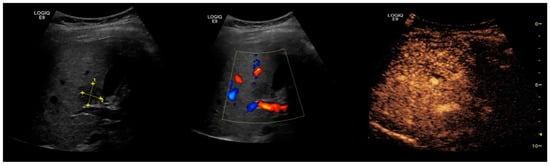

2.2. NAFLD-Related HCC: Could Conventional and Doppler US Differentiate between Focal Liver Lesions (FLLs)?

3. Contrast-Enhanced Ultrasonography (CEUS): An Add-on to the Diagnostic Power of Ultrasonography in NAFLD-Related HCC

3.2. Assessment of Fatty Liver Progression Using CEUS

3.3. The Evaluation of FLLs, Including HCC, in NAFLD Patients Using CEUS

3.3.1. Diagnostic Features of Hepatocellular Carcinoma on CEUS

3.3.2. HCC Particularities in NAFLD Patients